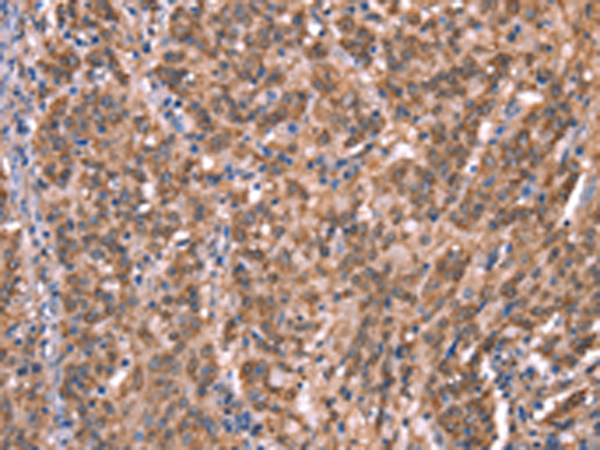

分类: 科研抗体货号: P04896别名: HGAL; GCAT2; GCET2应用: IHC反应种属: Human